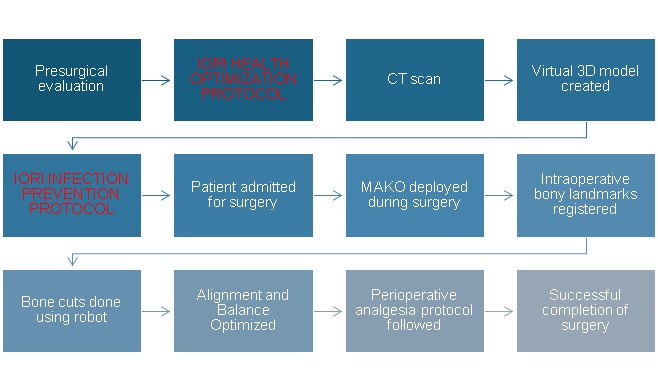

The workflow of a MAKO robotic knee replacement surgery is shown in the chart which will give an idea of how a robotic TKA helps in achieving the desired objective.